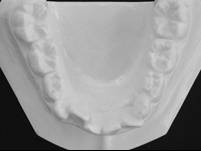

สภาพฟันก่อนรักษา

ขณะเข้ารับการรักษา ผู้ป่วยอายุ 11 ปี มีขากรรไกรล่างที่หลุบถอยไปด้านหลังอย่างมาก และถูกฟันหน้าบนกลางที่งุ้มเข้าครอบปิดทั้งหมด จะมองไม่เห็นฟันตัดล่างเพราะมีภาวะสบลึก กระดูกขากรรไกรบนและล่างเล็กอันจะสังเกตได้จากฟันหน้าบนและล่างซ้อนเกอย่างเห็นได้ชัด